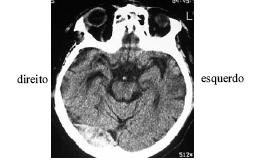

Após ter sofrido queda de um cavalo, um senhor de 55 anos de idade foi levado imediatamente ao pronto-socorro, onde se verificou, além das escoriações no corpo, pequeno hematoma subgaleal em região temporoparietoccipital direita. Foi medicado com analgésicos e antiemético. Após vinte minutos, os sintomas foram aliviados e o paciente solicitou alta hospitalar. O clínico geral solicitou o parecer do neurologista visto que os socorristas relataram perda de consciência, fato negado pelo paciente. Passadas 4 horas do trauma, o paciente mostravase inquieto, mas negava cefaléia ou náuseas. Foi levado para realização de tomografia computadorizada, cujo resultado é mostrado na figura acima. Na presença do neurologista, o paciente solicitou alta hospitalar, informando que morava a apenas 25 km do hospital e voltaria se houvesse piora. Diante de situação como a apresentada, após analisar o exame de imagem e o caso clínico, o neurologista deve